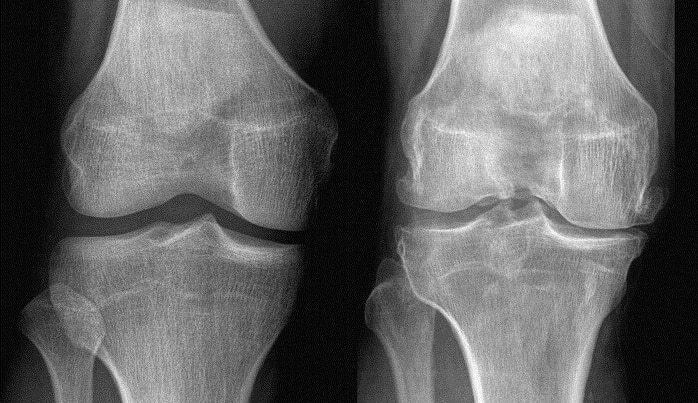

• Paziente: Donna, 68 anni, OA di grado III Kellgren-Lawrence.

• Sintomatologia: Dolore acuto al carico, atrofia marcata del vasto mediale. La paziente riferiva di stare quasi sempre seduta per “non consumare l’osso”.